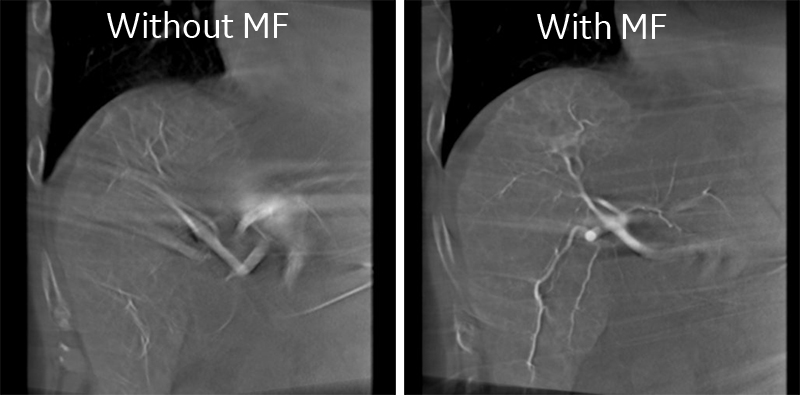

IGS630_Tokaidaigaku_01.jpg図1.肝動脈造影のCOR画像

左側:息止め不良の再構成画像

右側:MF使用時の再構成画像

“Motion Freeze”は画像を見て頂ければ多くの説明は必要ないかと思うが、簡単に説明するならば息止め不良のCone Beam CT画像を再構成する際にMotion Artifactsを低減するアプリケーションである(図1).